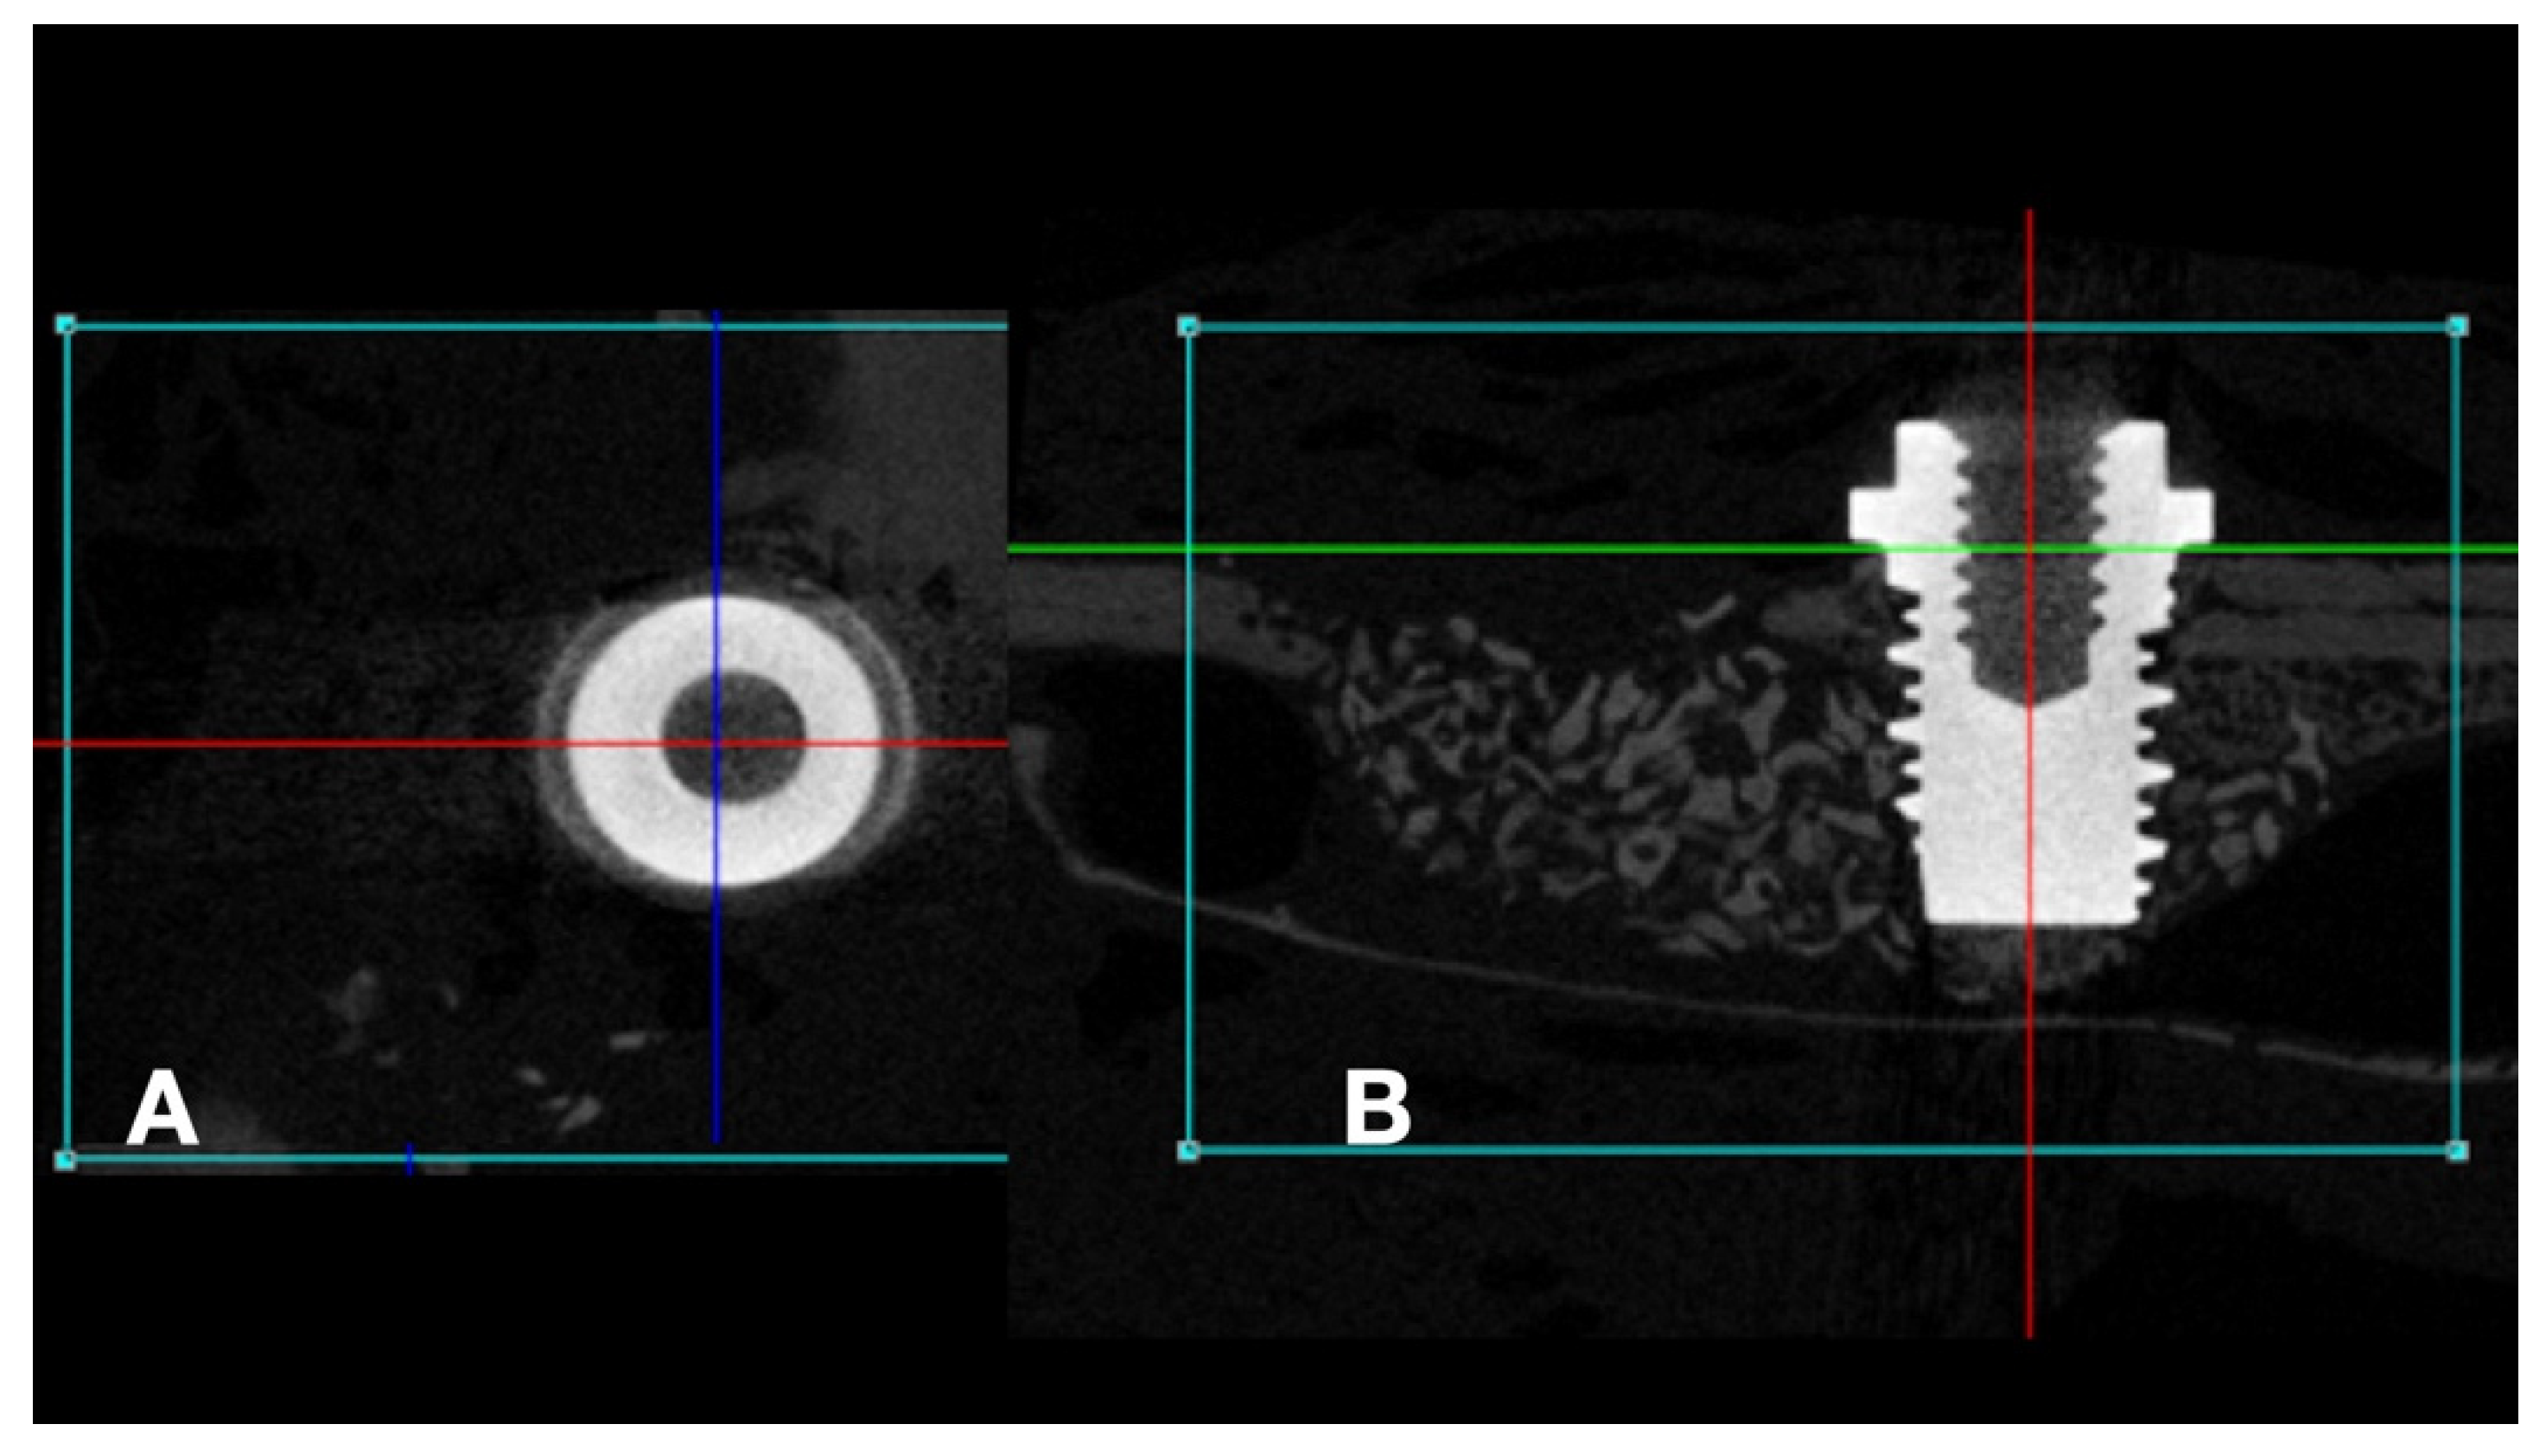

After 48 h of fixation in 10% buffered formaldehyde, the samples were scanned using the high resolution SkyScan 1172-160 micro-CT microtomograph (Bruker, Kontich, Antwerp, Belgium) to obtain two-dimensional tomographic projections and three-dimensional reconstruction. All scans were obtained at 100 kV and 100 μA, using an aluminum-copper filter to optimize the contrast, and set at 5.87 mm pixel size, 360° rotation, and a rotation step of 0.40. Two-dimensional tomographic projections and three-dimensional reconstruction were performed using the NRecon software (NRecon v.1.6.10.4, Bruker, Kontich, Antwerp, Belgium) and the implants were positioned on their long axis using the DataViewer software (v.1.5.0, Bruker, Kontich, Antwerp, Belgium), where it is possible to move and visualize the three axes (coronal, axial, and sagittal) (Figure 2). The axis of interest (sagittal) was selected for the complete visualization of the implants.

Figure 2.

Microtomographic images: (A) (axial) and (B) (sagital). (A): Red line = anterior-posterior cut, Blue Line = latero-lateral cut; (B): Green line = axial cut, Red line = latero-lateral cut.